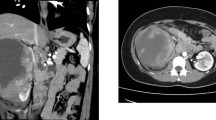

A 35-year-old Chinese female presented to the hospital for cough in October 2020. A computed tomography (CT) scan revealed a large right-sided renal mass and multiple enlarged lymph nodes (Fig. 1A); the tumor was determined to be malignant. The patient subsequently underwent laparoscopic resection of the right kidney. Postoperative pathology revealed 2 type 2 papillary RCCs with papillary and tubular structures and was classified as World Health Organization/International Society of Urologic Pathologists grade III (Fig. 1B). At 3 months after surgery, CT revealed multiple nodes in both lungs suggestive of metastasis (Fig. 1C). Immunohistochemistry indicated high expression levels of PD-L1 (tumor cells + 20%, Dako 22C3) (Fig. 1D). Because she had a medical history of uterine leiomyomas in 2018, HLRCC was suspected. Next-generation sequencing of genomic DNA from tissues and blood was performed after the patient provided informed consent (Geneplus-Beijing). The sequencing results revealed a previously unidentified germline nonsense mutation in exon 8 of the FH gene (c.1126 C > T; p.Q376*). Sanger sequencing confirmed these findings (Fig. 2). Then, whole-exome sequencing of genomic DNA was performed for other members of the patient’s family, and the variant was also detected in her grandmother, father, younger brother, and son. The germline nonsense mutation was searched in the Human Gene Mutation Database (HGMD), ClinVar database, and Genome Aggregation Database. This variant was classified as a pathogenic mutation in the ClinVar database; no previous study has reported this nonsense mutation, but an FH p.Q376P germline mutation was identified and classified as pathogenic [15]. Therefore, these findings supported a diagnosis of HLRCC-RCC.

Diagnosis of hereditary leiomyomatosis and renal cell cancer-associated renal cell carcinoma (HLRCC-RCC). A. CT revealed a large mass in the right kidney. B. Hematoxylin–eosin staining showed renal cell carcinoma with papillary and tubular structures. C. CT revealed multiple nodes in both lungs and the pleura. D. Approximately 20% of the tumor cells exhibited programmed cell death-ligand 1 (PD-L1) expression